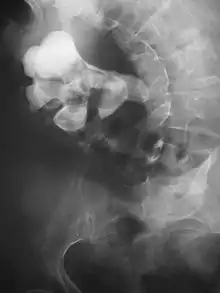

Radiograph showing a large staghorn calculus involving the major calyces and renal pelvis in a person with severe scoliosis

Stones that are large enough to fill out the renal calyces are called staghorn stones and are composed of struvite in a vast majority of cases, which forms only in the presence of urease-forming bacteria. Other forms that can possibly grow to become staghorn stones are those composed of cystine, calcium oxalate monohydrate, and uric acid.[85]